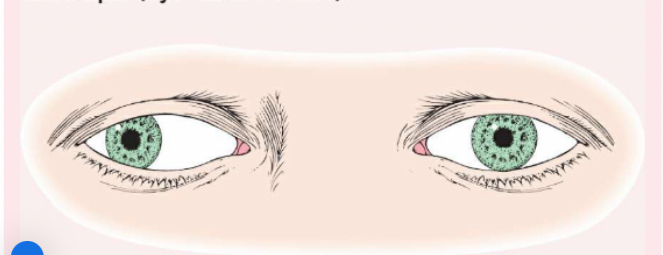

Pseudostrabismus

Normal in young children, the pupils will appear at the inner canthus (due to the epicanthic fold).

Strabismus (or Tropia)

A constant malalignment of the eye axis, is defined according to the direction toward which the eye drifts and may cause amblyopia.

Esotropia

(eye turns inward).

Exotropia

(eye turns outward).

Phoria (Mild Weakness)

Noticeable only with the cover test, is less likely to cause amblyopia than strabismus.

Esophoria

is an inward drift and

exophoria

an outward drift of the eye.